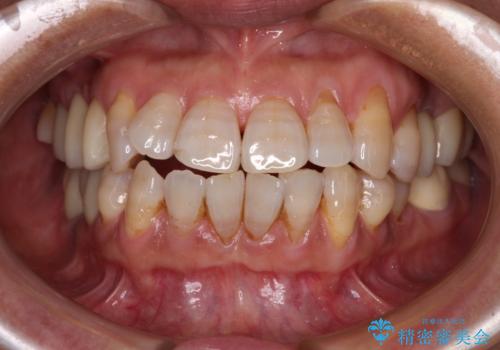

仮歯に置き換えた時点で歯肉からの出血は収まり、不快感が改善されました。

右下は、残存歯の状態があまり良くなかったため、今後抜歯となったことを想定して、最後臼歯のインプラントを決定しました。